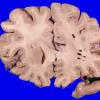

Artifact - Swiss Cheese Brain (3)